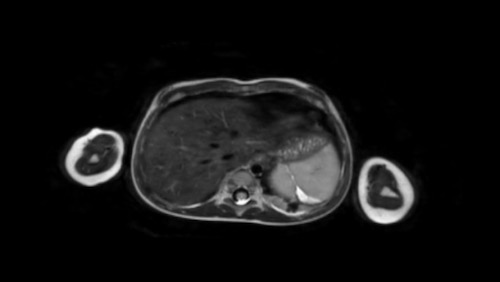

Mức độ lan rộng của khối u được đánh giá rõ ràng trên chuỗi xung TSE T2 weighted 3D theo mặt phẳng axial.

The left kidney is compressed and displaced caudally.

Có di căn hạch bạch huyết cạnh động mạch chủ (mũi tên vàng nhỏ).

Nguyên ủy của thân tạng và động mạch mạc treo tràng trên bị khối u bao quanh (đầu mũi tên).

Tĩnh mạch chủ dưới bị đẩy ra phía trước (mũi tên xanh).

Xẹp phổi hai bên ở vùng lưng thường được thấy trên MRI, vì việc kiểm tra được thực hiện dưới gây mê.